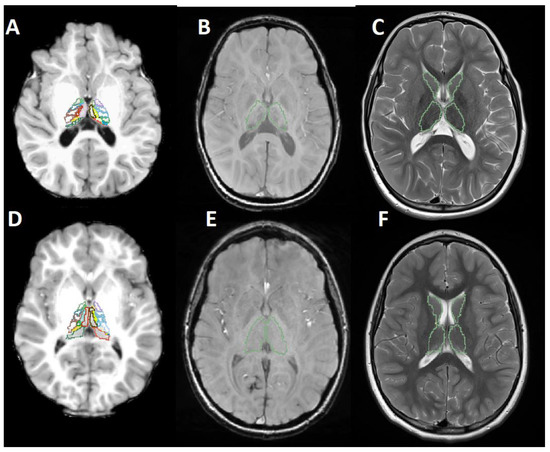

2.3. Image Segmentation and Feature Extraction